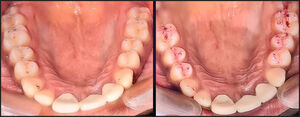

A single maxillary and mandibular occlusal view photograph were shot with indirect view using a mirror after being fully marked with articulating paper. A photograph was taken for both the 40-micron and the 100-micron thickness of articulating paper. None of the points were marked to authenticate further the double-blind study.

In this study, all participants observed 2 occlusal view clinical photographs, one with marks from 40-micron thickness of articulating paper and one with marks from 100-micron thickness articulating paper.

In both cases the darkest and largest markings in the photograph was chosen by the participants, suggesting that these were favoured selections because of the size of the marks and their dark colour and their prominence, which falsely indicated a “forceful” contact.1 They might have also been chosen because of where they were located on the teeth, such as being on an incline.1,2 This indicates that the participants were not able to truly discriminate different force levels when looking at the thickness or darkness of the paper makings. See Figures 1 and 2.